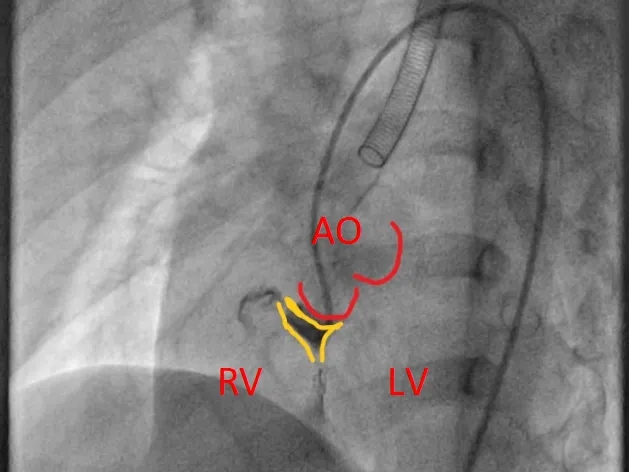

建立输送轨道

建立股动脉-VSD-股静脉轨道,沿泥鳅导丝送7F输送鞘至左室,选择6mm对称型、腰高7mm全降解封堵器。

左右盘面展开并锁定

左侧伞盘出鞘为球状,牵拉成型线后形态佳,后展开右盘,封堵器呈现“长哑铃状”,主动脉瓣少量反流。

轻轻牵拉成型线使封堵器成型,牵拉后左伞盘被拉进瘤腔内。

左右盘展开后,封堵器未锁定时造影可见封堵器中间少量反流,主动脉瓣少量反流。